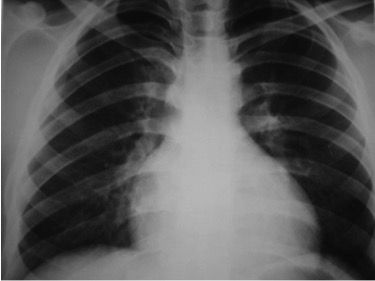

CASO: Febrícula y tos de 4 días de evolución.

Hallazgos:

- En la placa PA se observa una asimetría en los hilios pulmonares, el hilio izquierdo tiene una densidad aumentada.

- Tras examinar la placa lateral se observa un aumento de densidad en la columna que puede ser compatible con una condensación, es el signo de la desnificación vertebral.

SIGNO DE LA DENSIFICACIÓN VERTEBRAL: En la radiografía lateral normal, la densidad de la columna torácica tiende a disminuir desde la parte superior hasta el diafragma; la alteración de ese patrón por la presencia de una densidad superpuesta a la columna, indica la existencia de una consolidación pulmonar. Este signo adquiere especial valor cuando en la proyección posteroanterior la consolidación está oculta en el espacio retrocardíaco o en la base pulmonar.